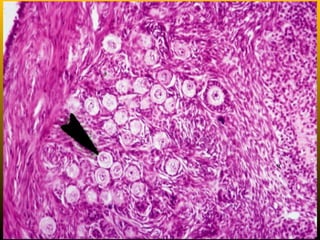

Follicular atresia or Degeneration

• Such degenerate follicles are called atretic

follicles. Sometimes they appear to contain a

dark pink-staining material which is probably the

remains of the zona pellucida of the follicle.

1. Oocyte showing signs of degeneration (multiple stages of this).

2. Stratum granulosa showing signs of disorganization.

3. Follicular cells separate from basal lamina and oocyte.

4. Glassy membrane (between granulosa and theca interna) is a

sign of advanced atresia.